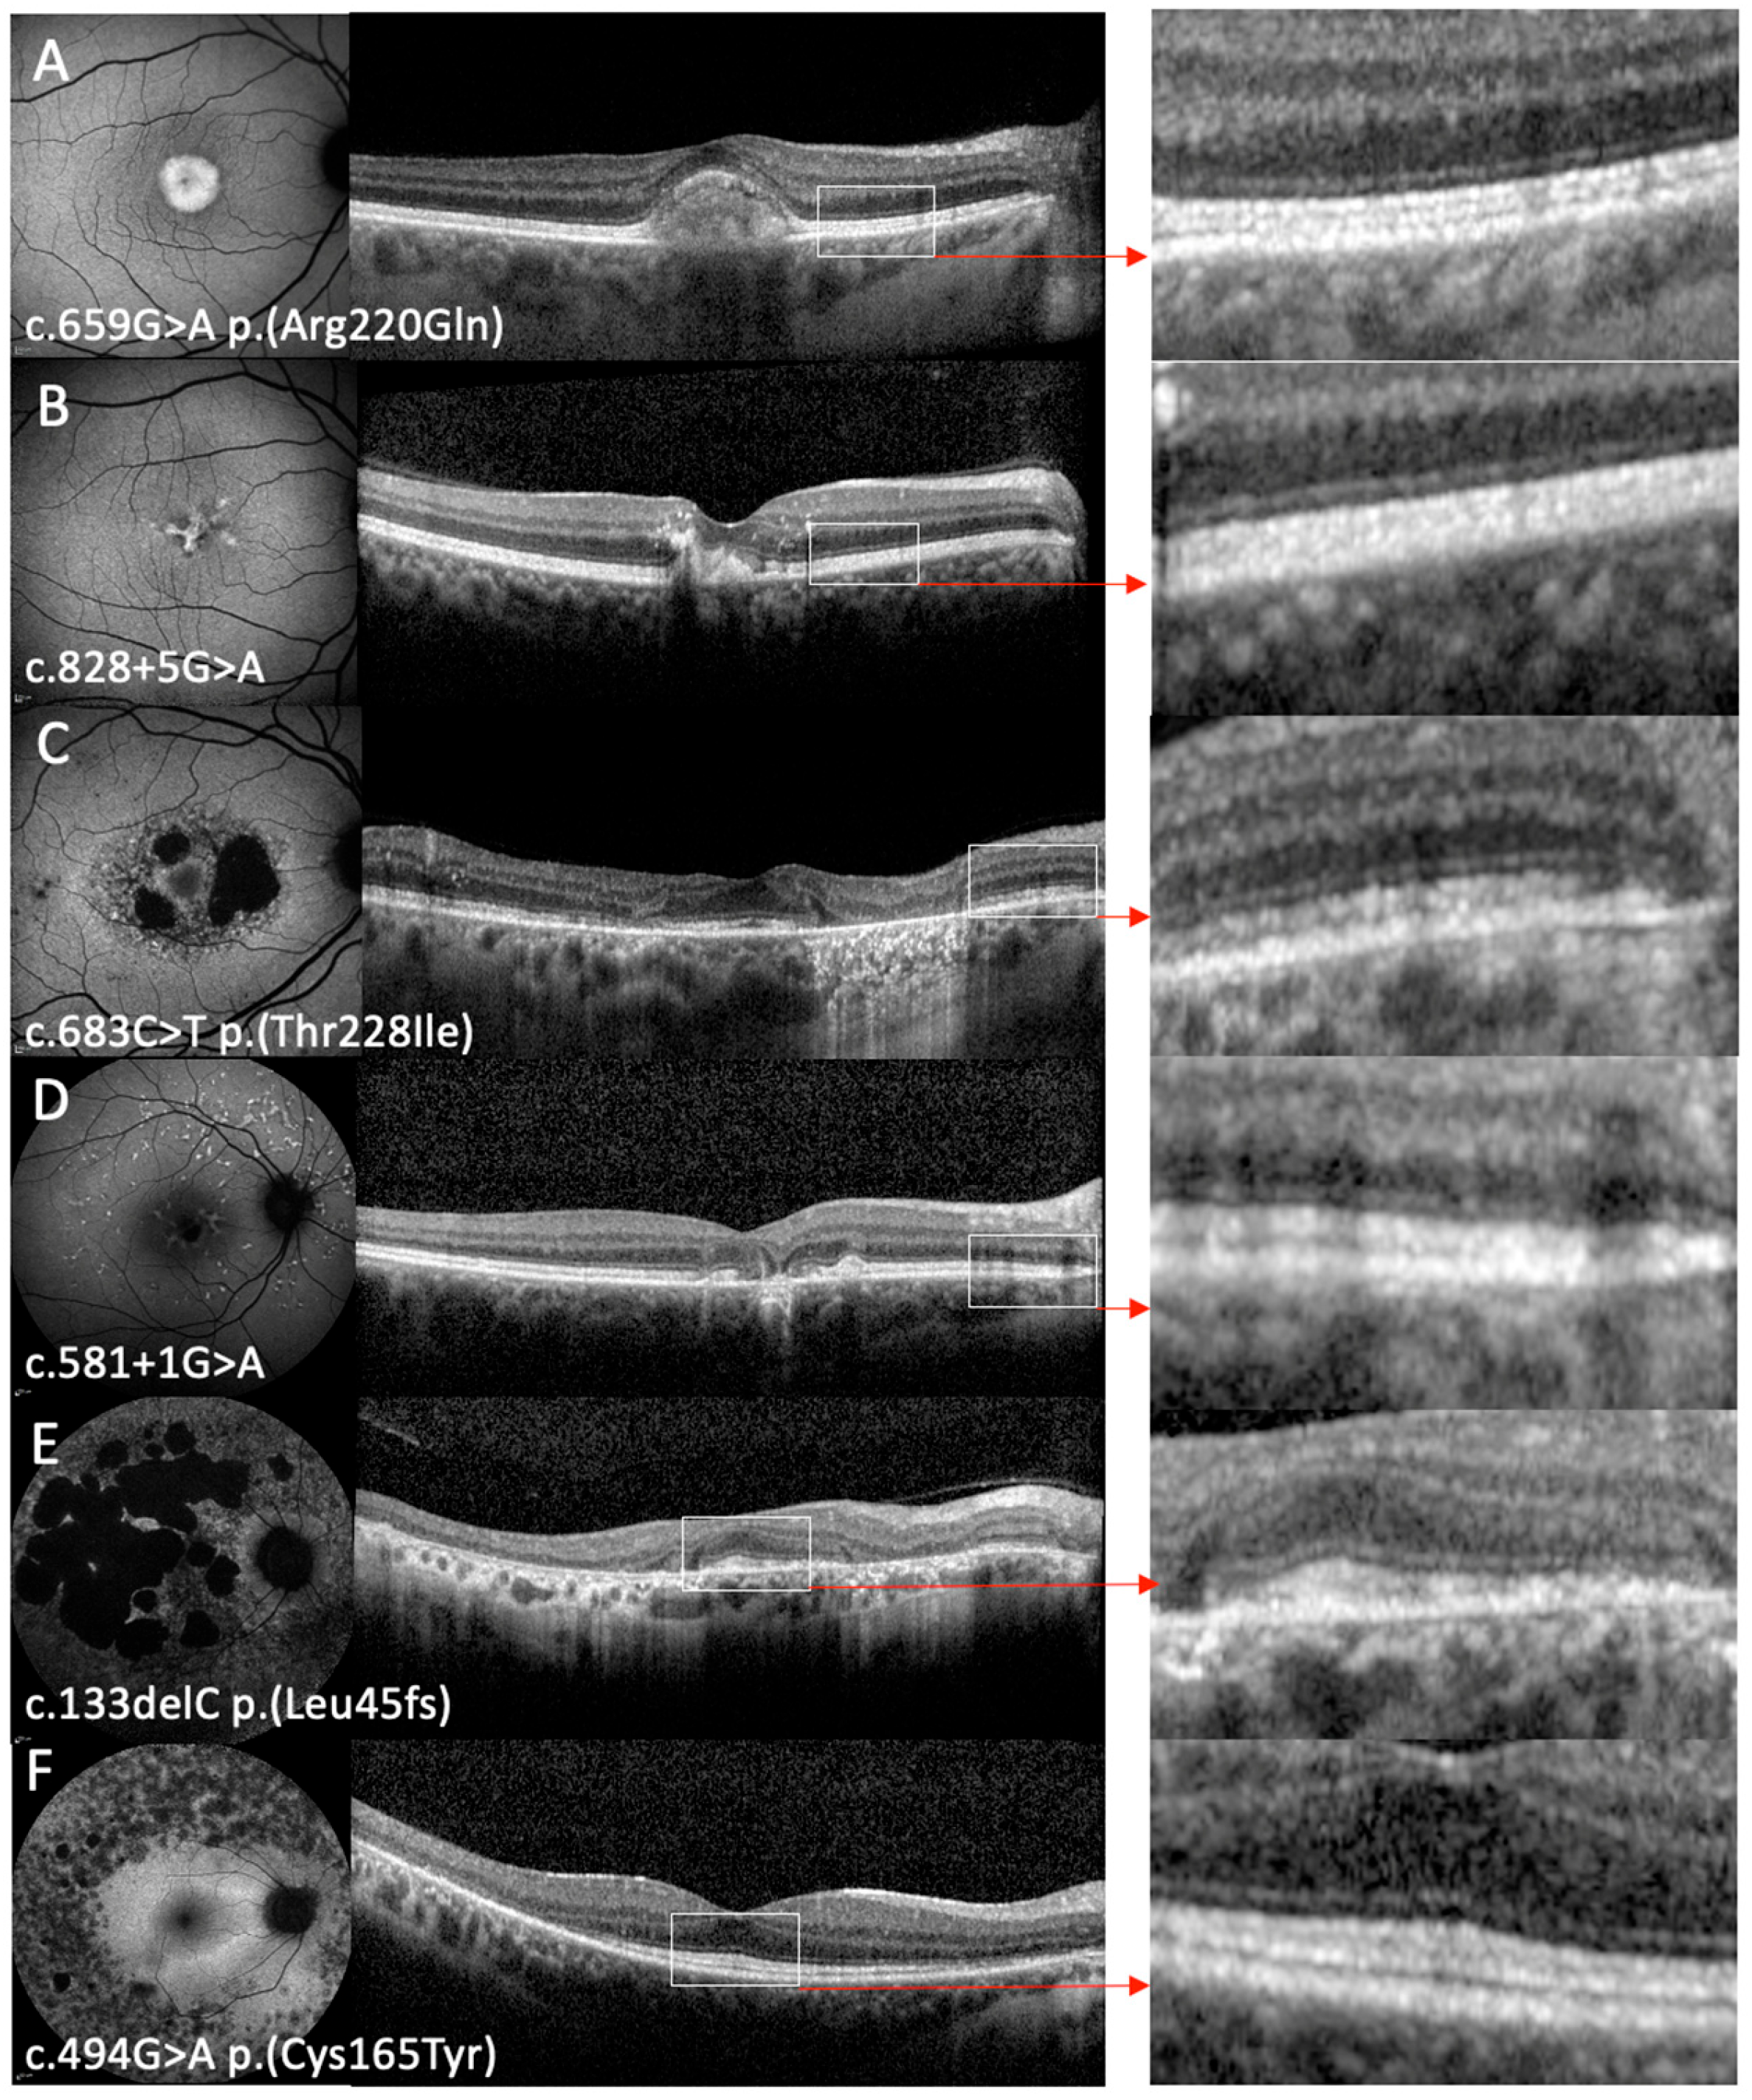

3.2. Phenotype on FAF and OCT Imaging

| 13A | c.659G>A | p.(Arg220Gln) | F | 56 | 50 | Visual distortion | AD (sister 13B) | 0.56 | 0.30 | 0.94 | 0.96 | 7 | AVMD OD  PD → AVMD OS  | AVMD |

| 13B | c.659G>A | p.(Arg220Gln) | F | 52 | 52 | Blurred vision | AD (sister 13A) | 0.30 | 0.10 | 0.78 | 0.28 | 9 | AVMD | AVMD |

| 18 | c.581+1G>A | Splicing | M | 52 | 52 | Central visual distortion and delayed dark adaptation | Sporadic | −0.08 | −0.06 | NA | NA | 0 | PSPD | Macular atrophy + flecks |

| 31 | c.133del | p.(Leu45fs) | F | 61 | 57 | Delayed dark adaptation, photosensitivity, constriction of peripheral fields, and Charles Bonnet | Sporadic | 0.1 | 0.1 | 0.3 | 0.18 | 7 | PSPD + heterogenous background AF | Macular atrophy + foveal sparing |

| 32 | c.494G>A | p.(Cys165Tyr) | M | 41 | 22 | Nyctalopia and constricted visual fields | AD | 0.00 | 0.00 | 0 | 0.00 | 6 | RP | RP |

| 33 | c.683C>T | p.(Thr228Ile) | M | 53 | 53 | NR | Sporadic | 0.08 | 0.00 | −0.20 | 0.18 | 1 | Atypical mottled perifoveal AF with patches of retinal atrophy | Macular atrophy + foveal sparing |